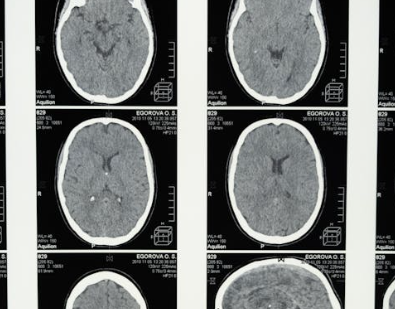

일반적인 MRI나 CT만으로는 진단이 어렵고, 다음과 같은 정밀 검사가 필요해요.

MRI & MRA로 뇌혈관 상태를 전체적으로 파악하고, 뇌혈관 조영술로 ‘연기처럼 피어나는 혈관’ 모양을 확인하며 SPECT 검사를 통해 뇌혈류 흐름을 측정해 수술 여부를 결정하게 됩니다.